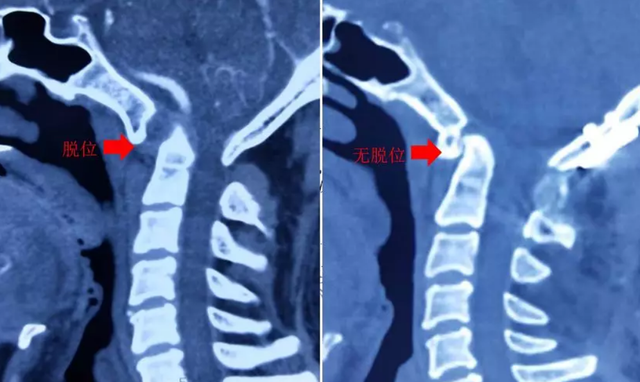

2. 儿童轻微外伤后或无显著原因,晨起后、感冒后出现的歪脖子、颈部疼痛、转头困难,很可能是因为“寰(huan)枢(shu)关节半脱”。

寰枢关节,就是人颈椎的第一节和第二节,由于儿童寰枢椎韧带松弛,轻微外伤或者姿势不良特别容易“关节脱位”。在脱位的时候,游离的枢椎齿状突(第二节颈椎),会压迫到脊髓,从而引起颈部疼痛、头晕、转头困难的症状。

但是儿童不善于表达、家长认知也不足,总是按照“落枕”给孩子按摩。本来孩子的寰枢椎已经不稳,大力的按摩,往往会加重病情,有的孩子居然生生被按成了高位截瘫、呼吸肌麻痹,甚至危及孩子生命。

图片

如果孩子头不能歪的症状持续了好几天,往往就不是“落枕”这么简单了,需要尽快去医院进行CT检查。一旦确诊,就要佩戴颈托,甚至需要手术治疗。